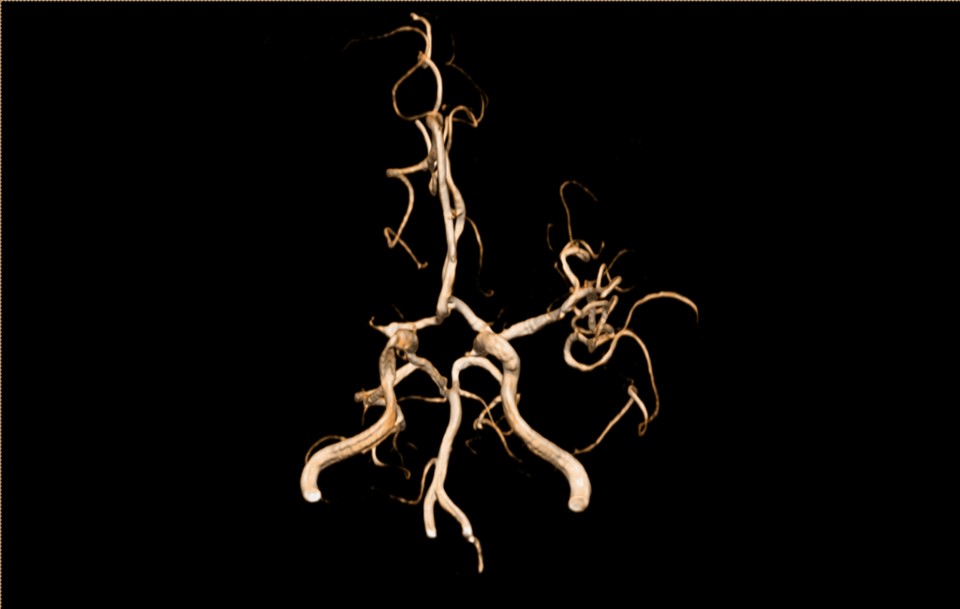

术后第2天CTA